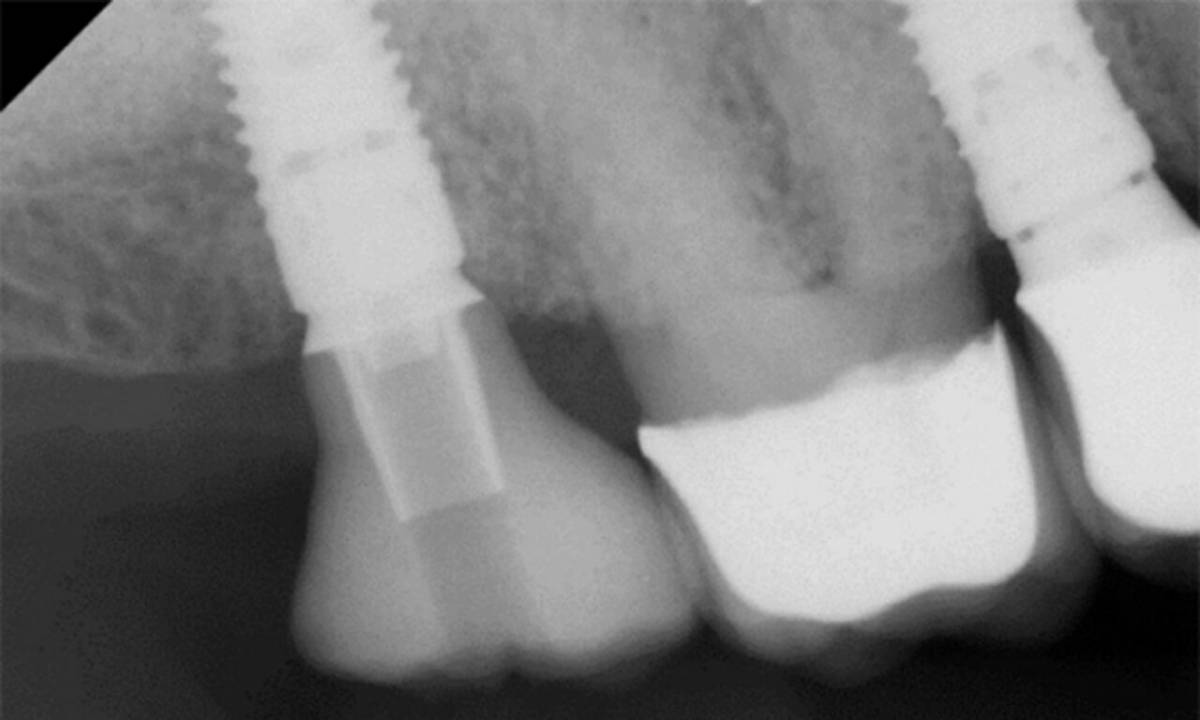

Von der analogen zur digitalen Implantatprothetik: Was ist sinnvoll und was ist Hype?

Dr. Peter Gehrke und ZT Carsten Fischer

Dr. Peter Gehrke und Zahntechniker Carsten Fischer erörterten im Teamwork die verschiedenen Indikationen und diskutierten die Frage, was digitaler Workflow eigentlich ist. Für viele sei das gleichbedeutend mit navigierter Planung, um darüber die Voraussetzung für eine fachgerechte prothetische Versorgung zu schaffen. Doch das sei nur ein Teil des digitalen Workflows. Zwar ist der Einsatz computergestützter Scan- und Fertigungstechnologien zur Herstellung von implantatgetragenem Zahnersatz oder Teilen für viele Anwender in Labor und Praxis bereits Realität. Doch allein schon die Modellkontrolle ist wieder analog ebenso wie es bei herausnehmbaren Arbeiten analoger Schritte bedarf. Auch wenn Intraoralscans für bestimmte Arbeiten analoge Abformungen überflüssig machen, stößt die digitale Abformung an ihre Grenzen, wo starke Angulationen prothetisch ausgeglichen werden müssen. Das gilt gleichlautend für suboptimal positionierte Implantate, die sich auf Basis von Intraoralscans nicht prothetisch exakt versorgen lassen. Ein digitaler Workflow funktioniere nur im Team, so Dr. Gehrke.

Intraorales Scanning ist weit mehr als nur Abformung, es ist Dokumentation und Qualitätskontrolle. Werden direkt nach Insertion die Implantatpositionen ins Labor übertragen, erhält der Zahnarzt ein unmittelbares Feedback als entscheidendes Kriterium vor der Anfertigung individueller CAD/CAM-Aufbauten in den Fällen, wo standardisierte Komponenten nicht mehr ausreichen. Mit individuellen Healing-Abutments lässt sich das gewünschte Emergenzprofil ausformen und die Daten können für die finale Versorgung übernommen werden. Das Risiko, die Mukosa durch die Krone zu stark zu verdrängen, ist damit ausgeschlossen: ein digitaler Workflow mit klinischem Nutzen.

Grenzen findet der digitale Workflow bei multiplen Implantaten und der frästechnischen Herstellung einer passiv sitzenden NEM-Brücke. Position und Ausrichtung der Implantate exakt abzuformen, gelingt nur analog, eine entsprechende intraorale Erfassung scheitert (noch) am inhärenten Mismatch der Scanbodies.